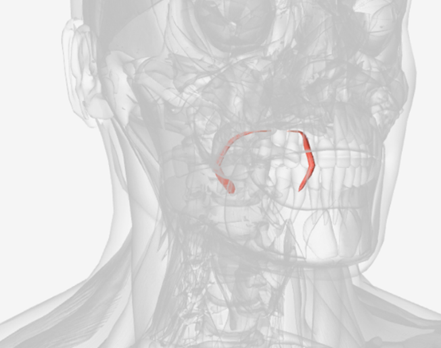

Cricopharyngeus

origin is the cricoid cartilage, coursing back to the orifice of the esophagus; function is to constrict the superior orifice of the esophagus; also referred to as the upper esophageal sphincter

Cricopharyngeus

|  |  |

Cricopharyngeus

D

Upper Esophageal Sphincter

Also know as the cricopharyngeus

cricopharyngeus

Also known as Upper Esophageal Sphincter